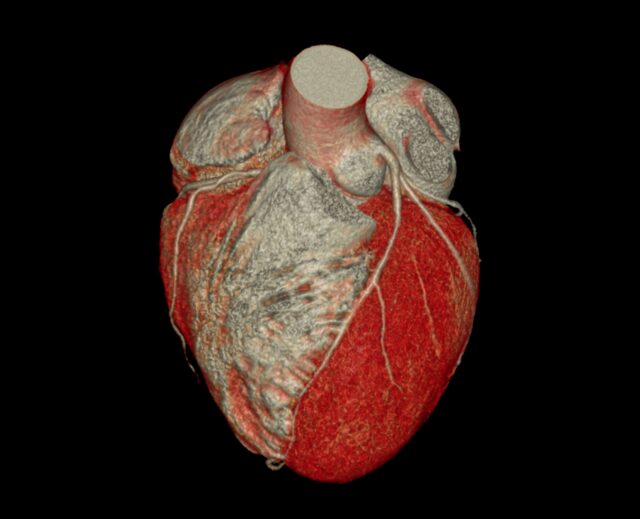

Computertomographie (Coronary Computed Tomographic Angiography : CCTA)